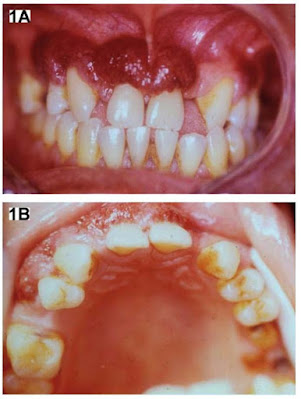

- Hiperplasia gingival (stramberry gingivitis). Figura 16